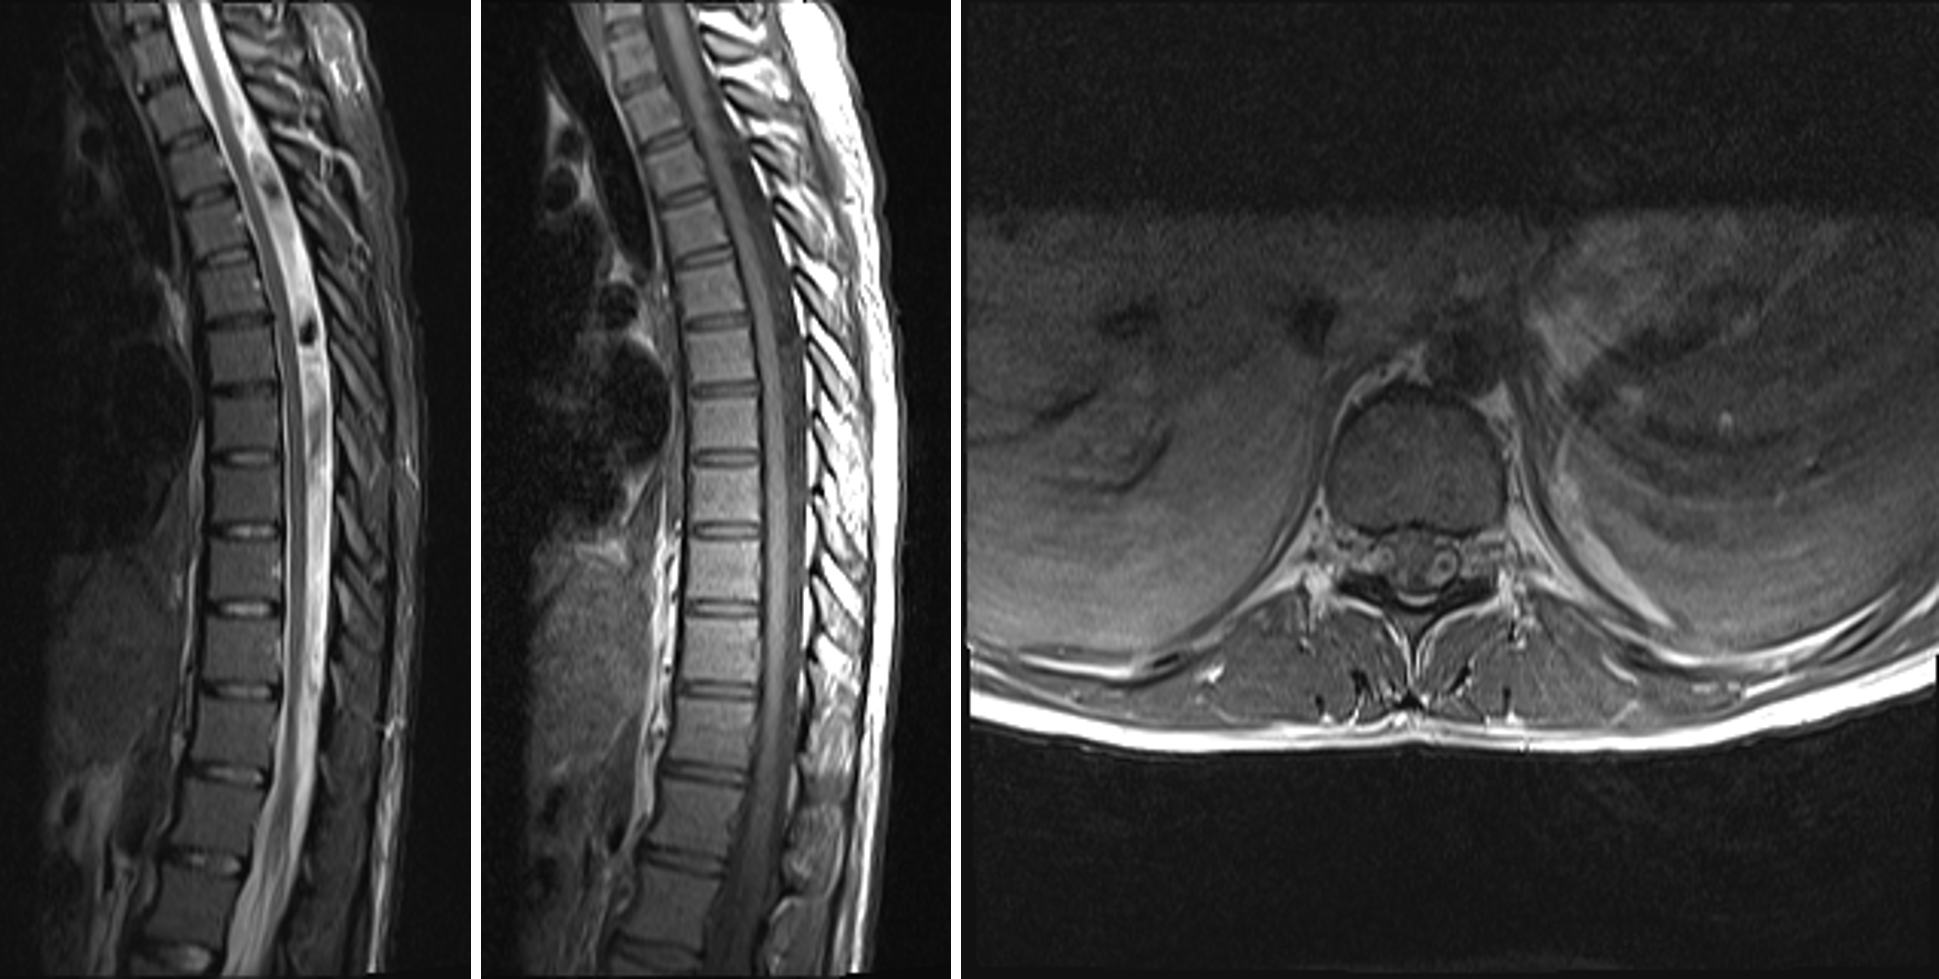

CSF pulsation artifact. (a) Axial T2weighted FSE MRI image (slice Prominent Motion Artifact important to recognize and understand motion artifacts to identify the physical cause of the problem in a particular. in this review, we first examine the physical origins of motion artifacts and then summarize the main. movement artifacts compromise image quality and may. we present a unique dataset of structural brain mri images collected from 148 healthy. Prominent Motion Artifact.